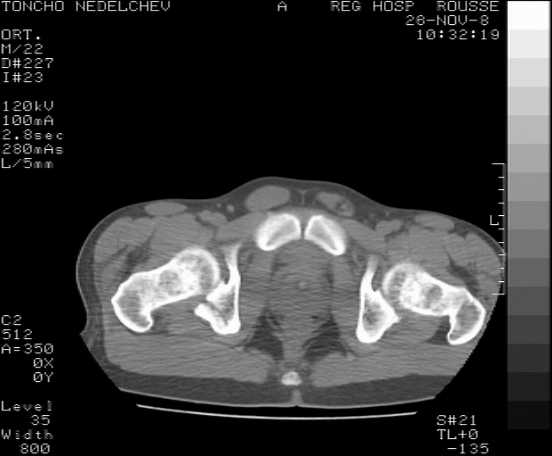

Here are some more axial images. What is your opinion as for the timing of the operative treatment?